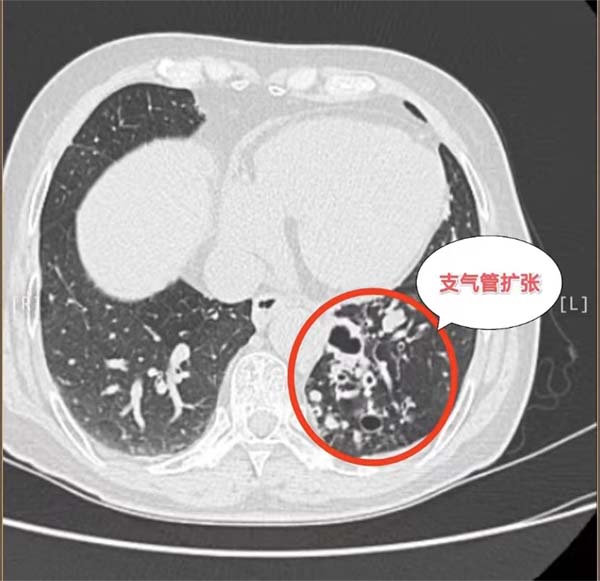

历经波折后求医无果,经多方打探,抱着最后一线希望杨女士和家人来到应急总医院胸外科求诊。胸外科副主任杨龙海博士从事胸外科专业多年,在肺癌方面具有丰富的诊治经验。杨龙海博士凭借丰富的临床经验,结合外院检查结果,排除远处转移,判断患者有手术的机会,且肺癌根治性手术远期效果相对较好,有治愈的可能。然而,肿瘤发现时已局部晚期,肿块巨大,侵犯到了左肺门大血管,侵犯纵隔及胸壁,加上患者伴有20多年的支气管扩张病史,致使患者症状较重,活动后气喘。这些因素导致手术需要切除整个左肺,手术难度及风险极高,切除过程会遇到肿瘤与肺门、纵隔、心包、胸膜等分离困难的难题,如果处理不当,可能出现大出血、循环呼吸衰竭等严重情况,随时危及生命。